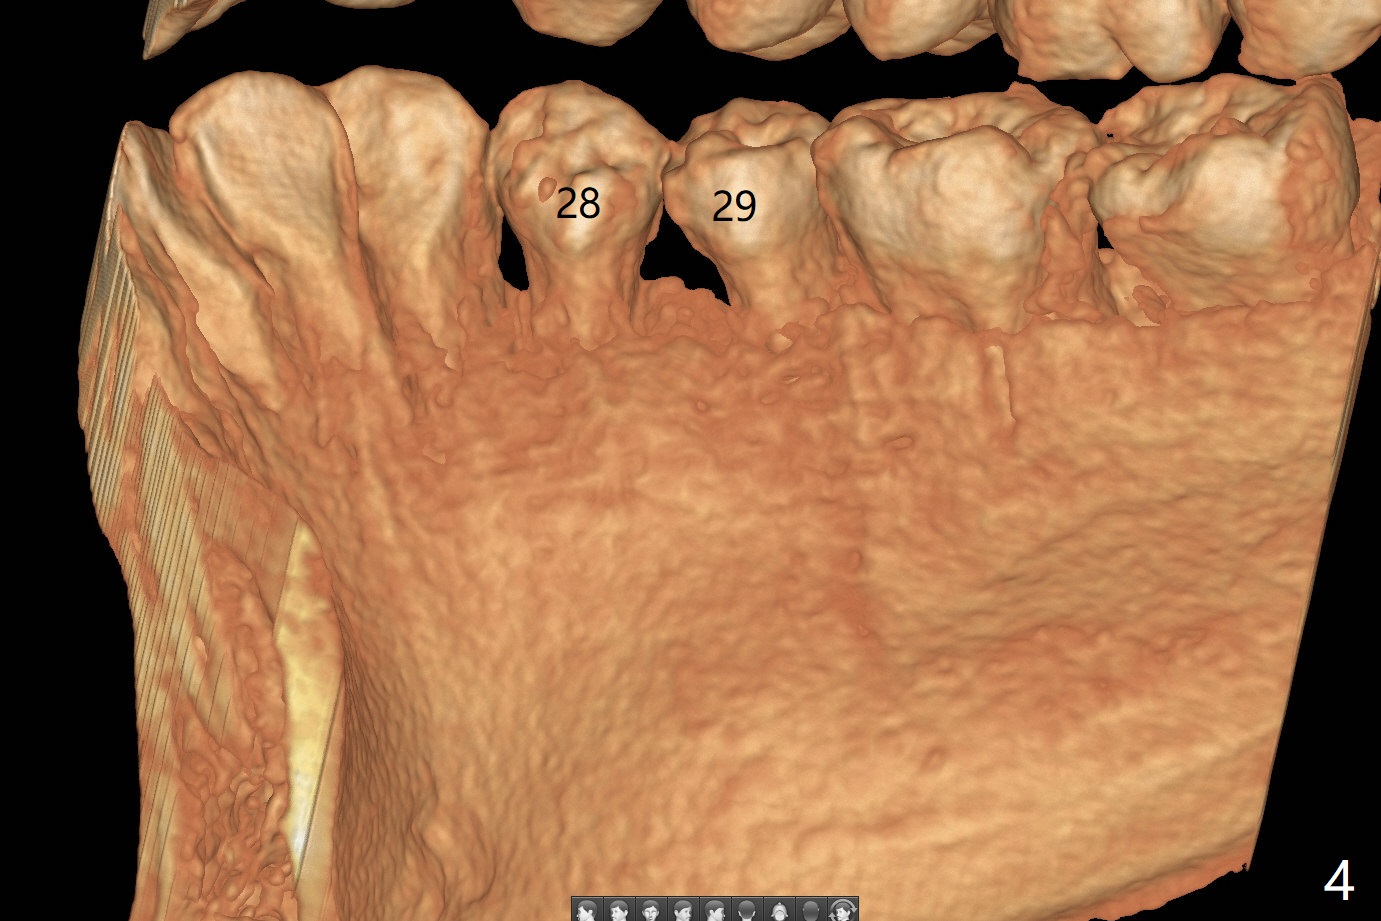

A 16-year-old woman presented to clinic with parents for orthodontic treatment for crowding (Fig.1).  How to treat the case with radiopaque lesion between LR 4 and 5?

CT is taken 4 months post panoramic X-ray (Fig.2).  C: coronal; S: sagittal; A: axial; B: buccal.  Coronal (Fig.6) and sagittal (Fig.7) sections.  It seems that the lesion does not invade the thin buccal plate or the periodontium.